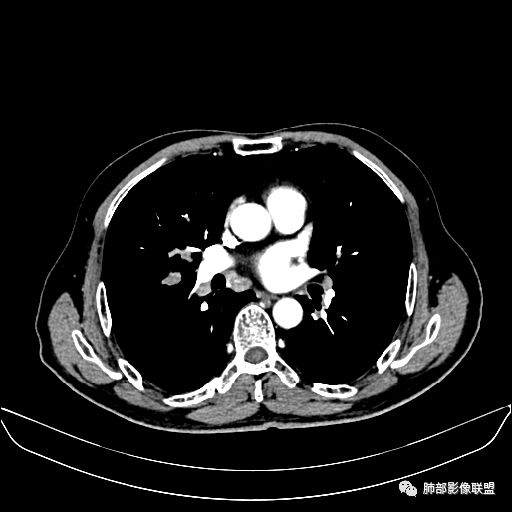

住院4天后行胸部增强CT

动脉期

老年男性,因“咳嗽咳痰1月余。”入院。病程中咳嗽咳痰,咳黄白痰,间断咯少许鲜红色痰血。PPD阳性。胸CT:右肺中叶外侧段支气管管腔阻塞,大片实性病变,病灶边缘光滑,部分边缘膨隆,可见分叶,肺门及纵隔可见肿大淋巴结,并可见钙化。增强可见病灶明显强化,而且延迟强化明显,病灶内多发低密度区,内见血管影,血管变细、部分血管破坏。考虑恶性病变可能性大,鉴别慢性肉芽肿性病变。

胸CT:跨叶大肿块,主体在中叶,右中叶外侧段支气管阻塞,病灶部分边缘膨隆,可见分叶,部分边缘平直,肺门及纵隔可见肿大淋巴结。增强病灶不均匀强化,延迟强化明显,病灶内多发低密度区,内见血管飘浮,部分血管变细、模糊。考虑:恶性病变可能性大,大细胞?淋巴瘤?鉴别慢性肉芽肿性病变。

右肺中叶软组织肿块,外围向内生长,叶间胸膜向前内移位,肿块近肺门侧跨叶,中叶外侧段支气管截断,密度不均匀,双侧肺门及隆突下见肿大淋巴结,增强后呈中度不均质强化,肺动脉供血,多发坏死区,边界尚清,坏死区域内见结构,结合病史考虑恶性,鉴别诊断1结核,爬行征是沿支气管树分布,外宽,内窄,周围有卫星灶,内气管狭窄后扩张,此例沿叶间胸膜长轴分布,气管有截断,不典型。2炎性肉芽肿,符合的地方下方层面增强后延迟性轻度环形强化,不符临床无发热等急性感染病史,实验室指标不符,病灶周围渗出及慢性炎性改变有,不明显。